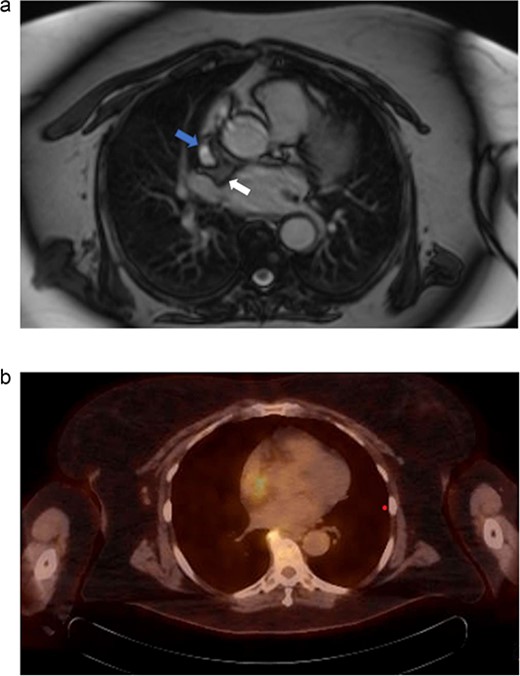

(a) MRI chest. Mass represented by white arrow. (b) PET/CT. Uptake is demonstrated in the mass associated with the SVC and right atrium.

We present another rare case of a hibernoma occurring just a few months later. A 63-year-old woman with history significant for HTN, COPD, GERD, ETOH abuse, and a 54-pack year tobacco use experienced continued weight loss of 70 lbs in the last 5 years. She underwent extensive workup for malignancy, which included MRI of the chest. MRI showed a 3.0 x 3.1 cm tumor circumferentially involving the superior vena cava at the atriocaval junction. This mass was hyperintense on T1 and T2-weighted images (Fig. 3a). Transesophageal echocardiogram was performed, and the mass was not appreciated. PET showed increased FDG uptake in the mass area without evidence of extracardiac disease (Fig. 3b). The recommendation was made for surgical resection.